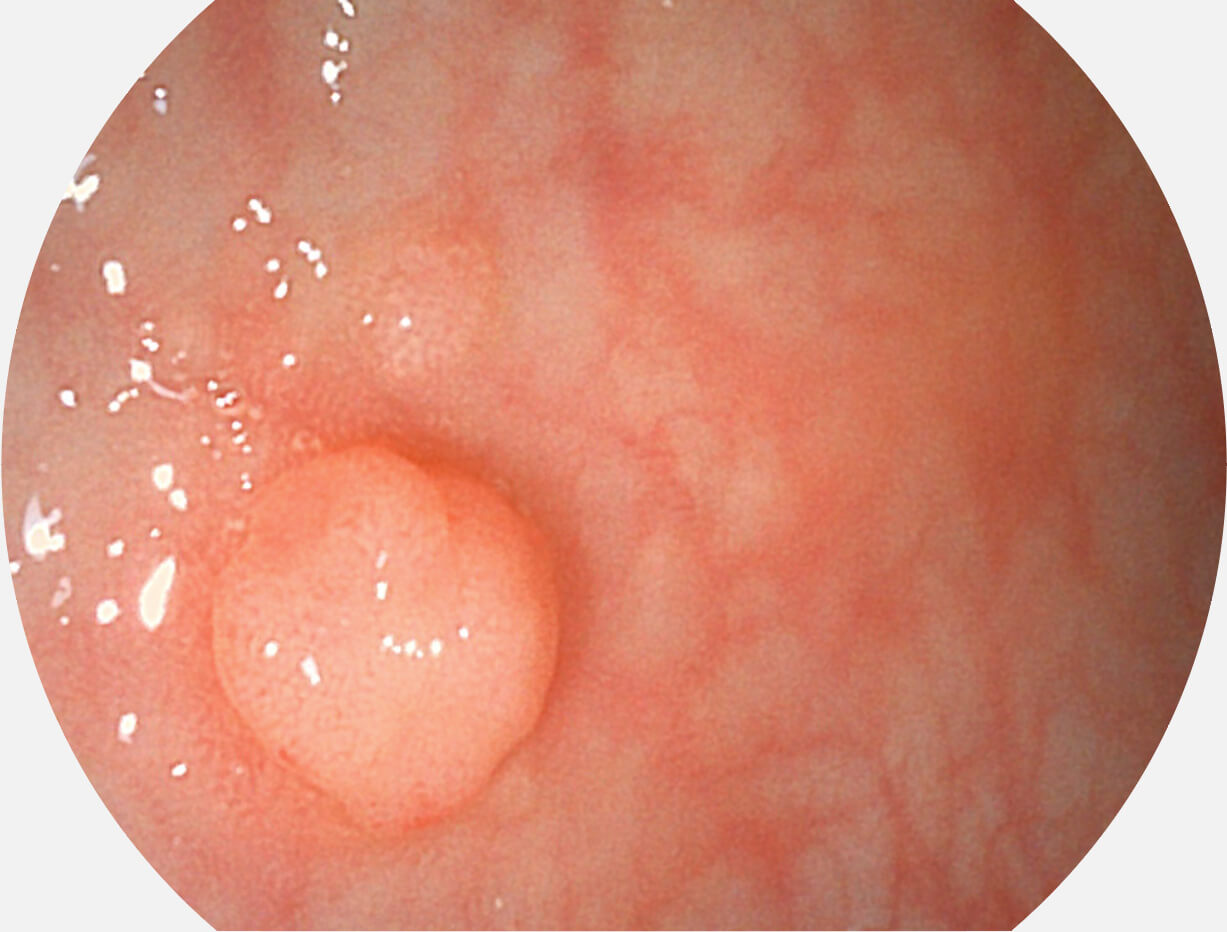

• 白光图像 SFI图像